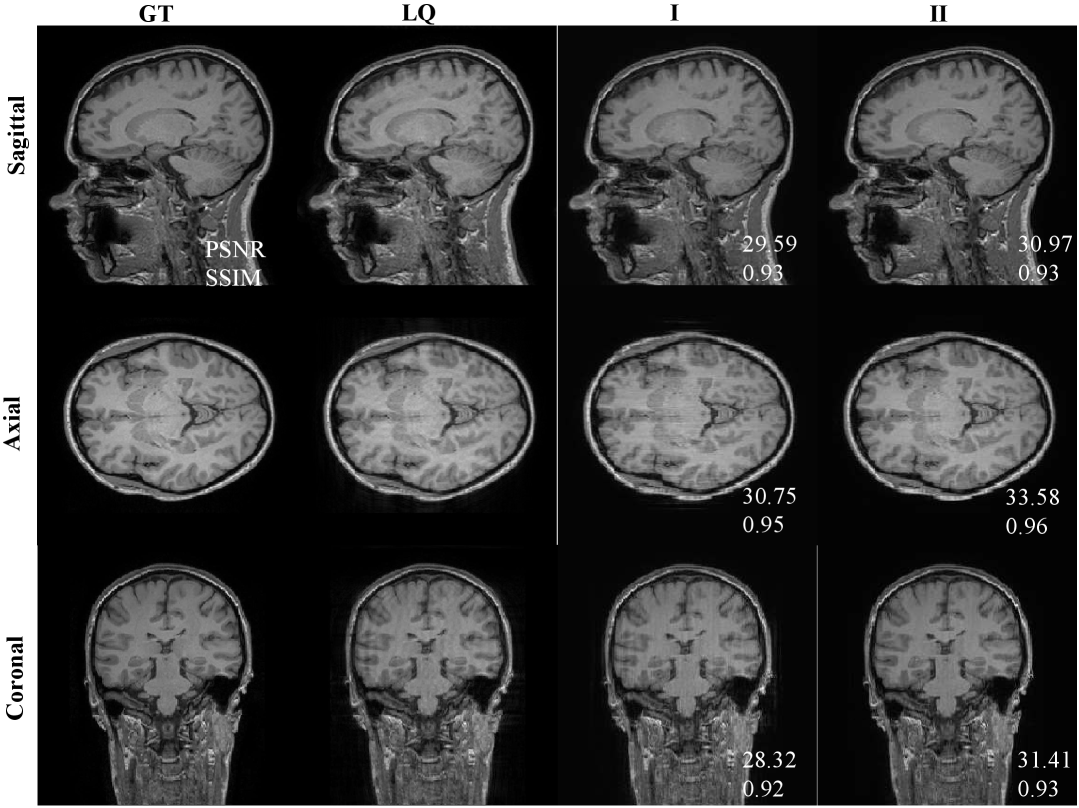

IV-D Performance Comparison on Actual Data

To verify the effectiveness of the algorithm in the real world, we deployed our algorithm and the comparison algorithms on real world data. The results are shown in Fig. 7. The 3DU-Net method benefits from paired learning and is effective at removing artifacts. However, current real-world data is not fully paired, causing the method to recover spurious structures that do not belong to the LQ images, which are most noticeable in the coronal plane. Furthermore, it exhibits significant over-smoothing compared to GT images. The BSA method is significantly more faithful to the LQ structure than 3DU-Net, but some errors in the results are also present, as shown by the red arrows. The SDE-MRI method can basically preserve the structure of the LQ images, but the regions indicated by pink arrows show insufficient artifact removal. This may be due to the inherent flaws of the method’s direct employment of weighted fusion. The PFAD method is better at removing artifacts than SDE-MRI, but significant structural errors and inter-slice discontinuities are observed, as indicated by the red arrows. This also reflects the imperfections of the two diffusion model-based methods in terms of structure preservation and artifact removal. In contrast, our method exhibits the capability to remove artifacts while preserving details in the LQ images even with unpaired data. This is due to the fact that our method does not learn the correspondence between the LQ images and the ground-truth images, but rather learns the degradation process from an image with motion artifacts to one without such artifacts. Furthermore, our pseudo-3D learning strategy avoids the inter-layer discontinuities that arise in 2D learning.

We randomly selected ROIs and evaluated the PSNR and SSIM metrics of several algorithms, as shown in Fig. 7. Because the 3DU-Net method completely learns the characteristics of the ground truth (GT) and fails to retain the key features of the LQ images, we believe that comparing its objective evaluation metrics against the GT is meaningless. Finally, our algorithm also exhibits significant advantages in terms of objective evaluation metrics.